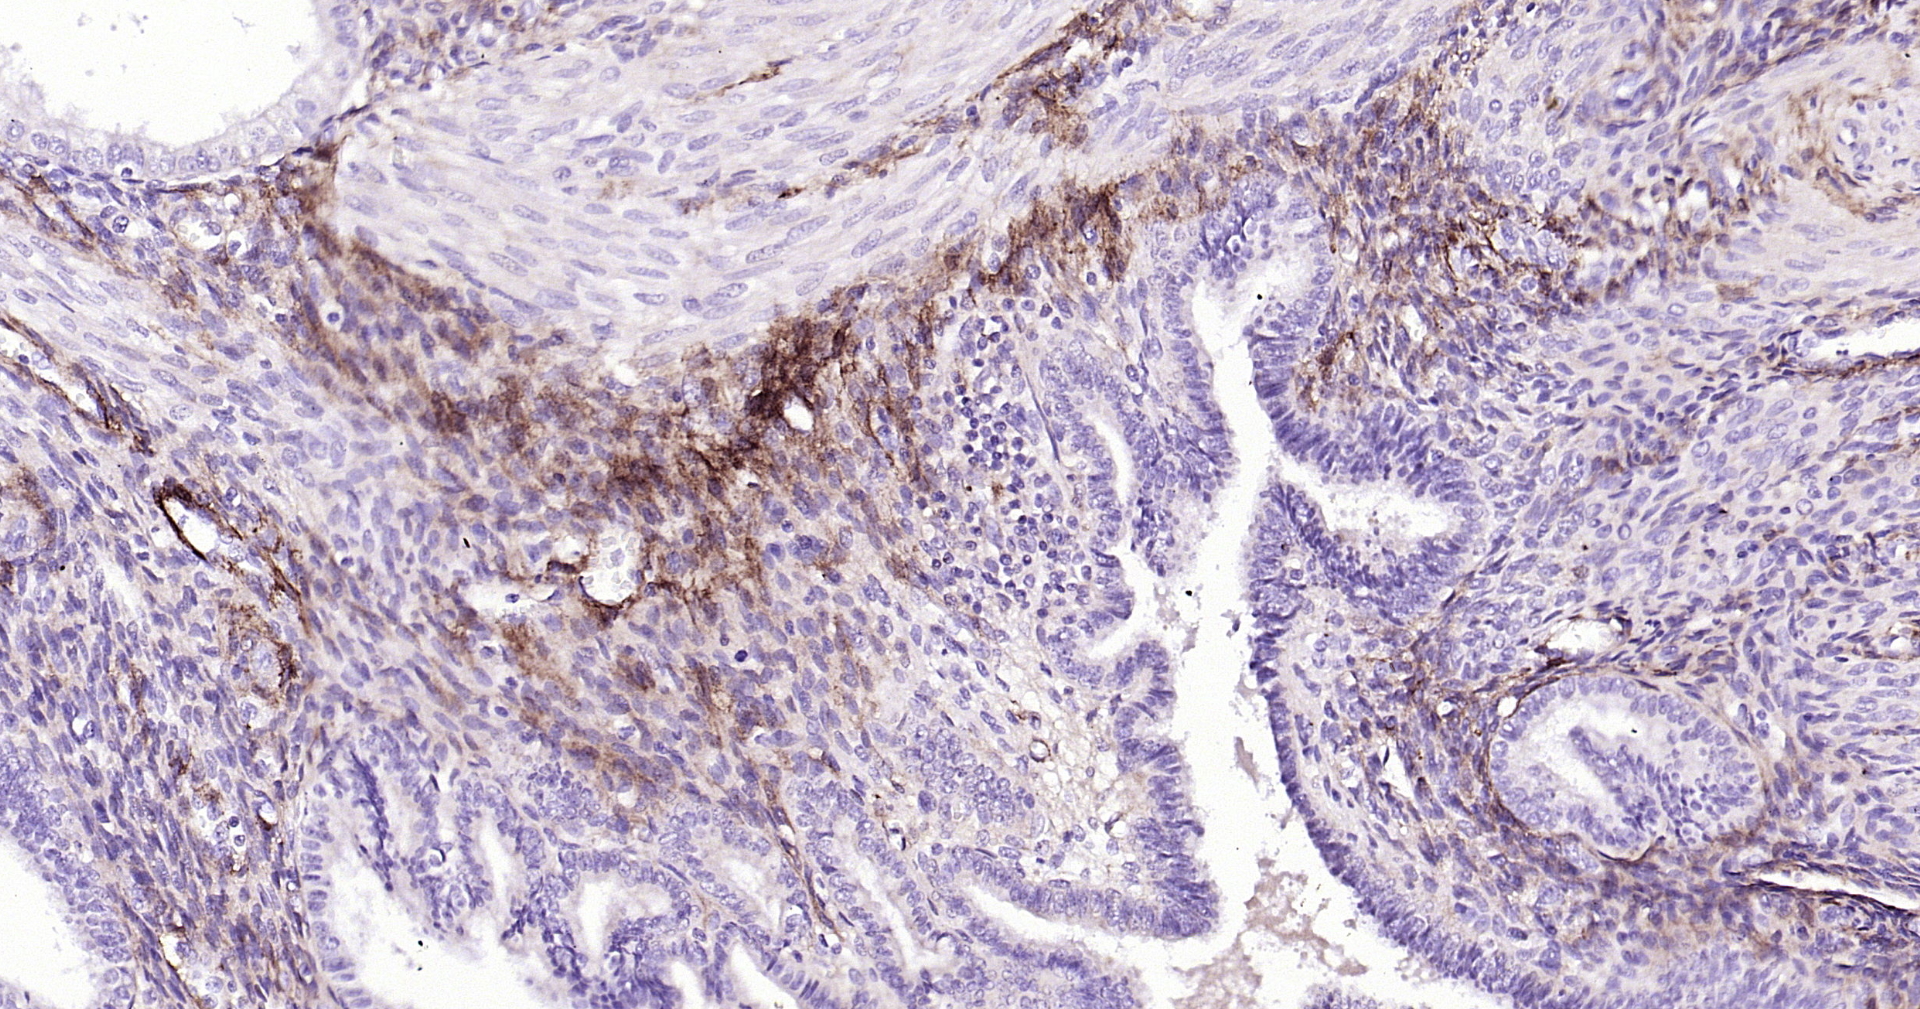

• IHC-P

IHC-P 1:100-500